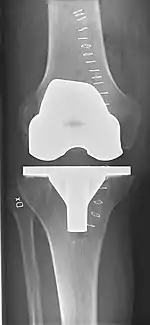

X-ray of total knee replacement, anteroposterior view (left) and lateral view (right)